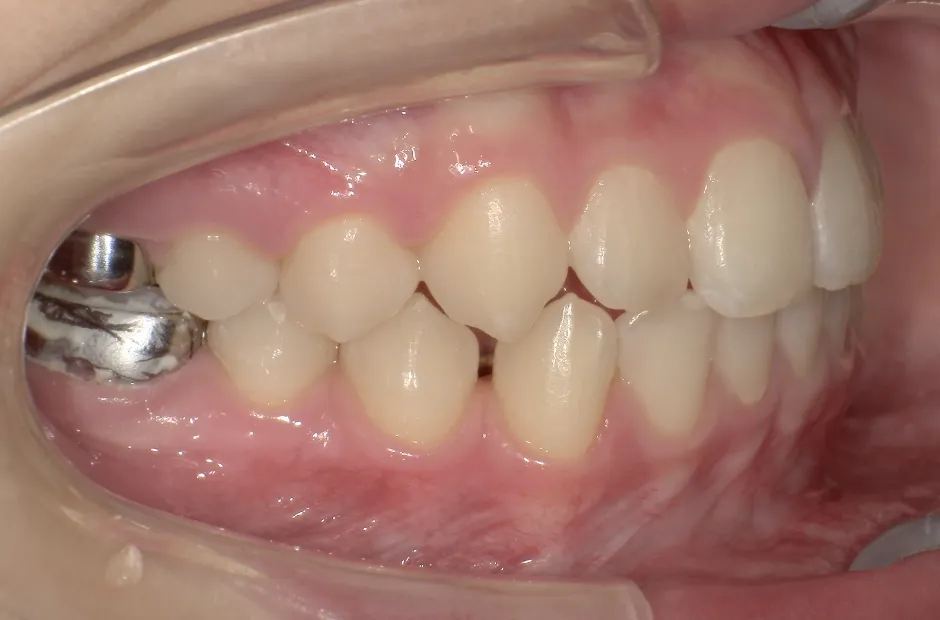

反対咬合

| 診断名・主訴 | 前歯反対咬合 |

|---|---|

| 年齢・性別 | 12歳・男性 |

| 治療期間・回数 | 1年半 18回 |

| 治療に用いた主な装置 | リンガルアーチ(前方誘導弾線) |

| 抜歯部位 | なし |

| 治療費 | 35万円(税抜) |

| リスク・副作用 | 装置による違和感・疼痛・歯肉退縮・歯根吸収・虫歯のリスクなど |